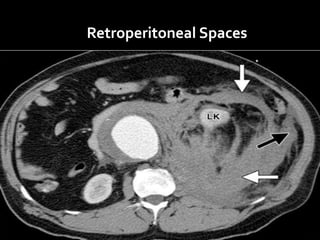

Retroperitoneal Spaces

S = Suprarenal (adrenal) Glands

A = Aorta/IVC

D =Duodenum (except the

duodenal cap- first 2cm)

P = Pancreas (except the tail)

U = Ureters

C = Colon (ascending and

descending parts)

K = Kidneys

E = (O)esophagus

R = Rectum

Retroperitoneal organs